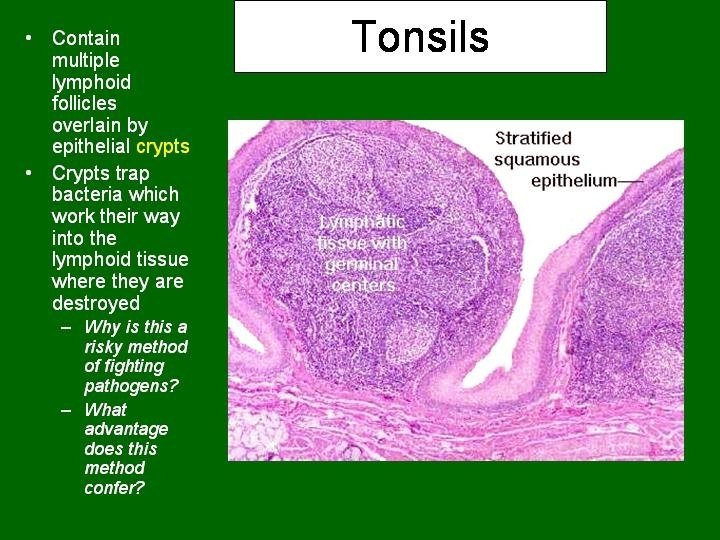

TONSILS These incompletely encapsulated lymphoid aggregates contain many lymphoid nodules; they underlie the mucous membranes (epithelial lining) of the mouth and pharynx. Together with the diffuse subepithelial lymphoid tissue that connects them to form a ring, they guard the common entrance to the digestive and respiratory tracts. The 3 types, palatine tonsils, the pharyngeal tonsil, and lingual tonsils, differ in number, epithelial covering, presence (or absence) and number of epithelial invaginations or crypts, and presence (or absence) of a definitive partial capsule. Most specific structures: epithelial linings, lymphatic nodules under the epithelium with lymphatic infiltration and crypts.

Tonsils

Tonsil

Palatine Tonsil